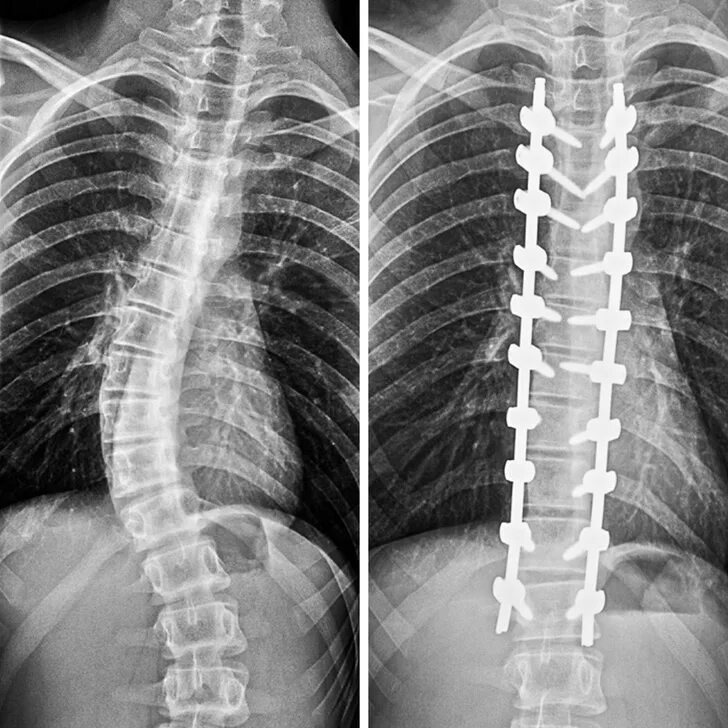

Сколиоз хирургия